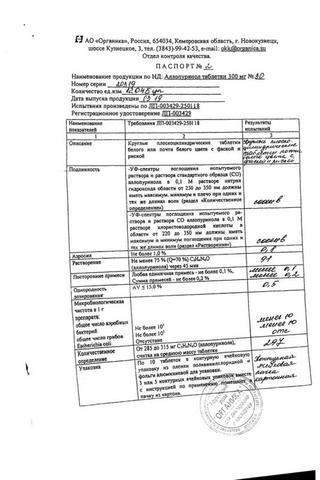

Аллопуринол таблетки 300 мг 30 шт

Аллопуринол: Состав

Таблетки белого или белого с желтоватым оттенком цвета, круглые, плоскоцилиндрические, с риской и фаской.

1 таб.

аллопуринол 100 мг

Вспомогательные вещества: целлюлоза микрокристаллическая (МКЦ-101 Премиум) - 54 мг, крахмал кукурузный - 25 мг, карбоксиметилкрахмал натрия - 10 мг, повидон К25 - 8 мг, кремния диоксид коллоидный - 1 мг, магния стеарат - 2 мг.

10 шт. - упаковки ячейковые контурные (1, 2, 3, 4, 5, 6, 7, 8, 9 или 10 шт.) - пачки картонные.

14 шт. - упаковки ячейковые контурные (1, 2, 3, 4, 5, 6, 7, 8, 9 или 10 шт.) - пачки картонные.

25 шт. - упаковки ячейковые контурные (1, 2, 3, 4, 5, 6, 7, 8, 9 или 10 шт.) - пачки картонные.

30 шт. - упаковки ячейковые контурные (1, 2, 3, 4, 5, 6, 7, 8, 9 или 10 шт.) - пачки картонные.